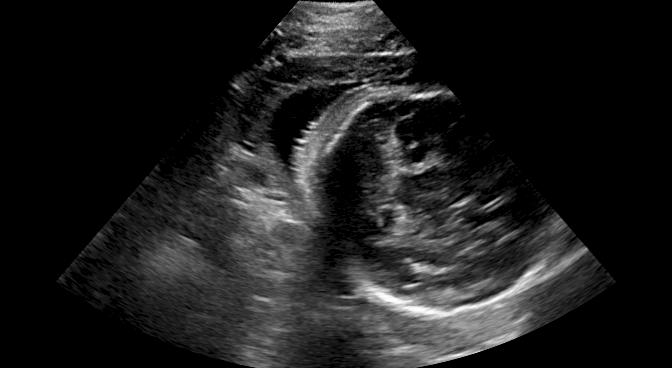

Fig. 9 qualitatively shows that shadow confidence maps are able to improve the performance of US image fusion algorithms with different weighting strategies. Fig. 9 also shows the difference between adding two different types of confidence maps. These two types of confidence maps are generated by the confidence estimation network which are separately trained by either MSE or Sigmoid loss. Fig. 9 (a) to (d) illustrate image fusion results for the same case using different combinations of weighting strategies and loss functions. The difference maps indicate that shadow confidence maps are capable of improving image fusion performance. Fig. 9 (e) to (h) show image fusion results on four different cases. We randomly select two positively affected cases (Fig. 9 (e) and (f)) to show visual improvement. We additionally show two randomly selected examples (Fig. 9 (g) and (h)) that don’t show perceptually significant improvements after adding shadow confidence maps. Quantitative evaluation for image fusion is not possible because of lacking a ground truth for US compounding tasks.

V-C Automated Biometric Measurements

We integrate our shadow confidence maps into an automatic biometric measurement approach [32], and show the biometric measurement performance (measured by DICE) before and after adding shadow confidence maps.

Similar to the ultrasound standard plane classification, shadow confidence maps are integrated into a biometric estimation model described in [32] as an extral channel. Specifically, we train and test four fully convolutional networks with the same hyper-parameters as detailed in [32], and use the same ellipse fitting algorithm described therein. The first network is trained only on the image data used in [32]. The other three networks are trained with an additional input channel for shadow confidence maps that are separately generated by the baseline, the proposed, and the proposedAG method.

We show three examples that are affected by shadows, and show their biometric measurement results in Table V. From this experiment, we find that biometric measurement performance is boosted by up to for problematic failure cases after adding shadow confidence maps. The average performance on the entire test data set stays almost the same since only a small proportion of the test images are affected by strong shadows, mainly because of the image acquisition by highly skilled sonographers.